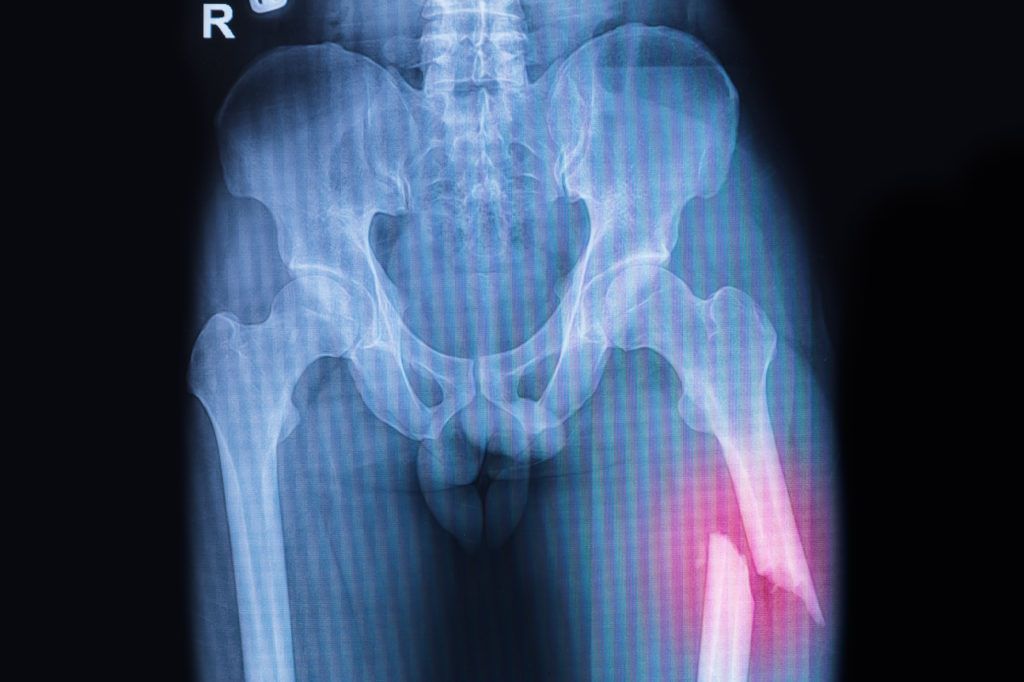

Note: This is a stock photo of an X-ray showing a broken femur.